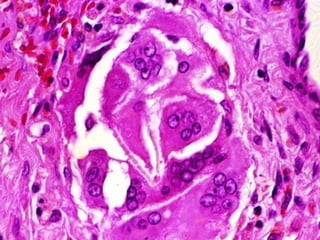

REACCIÓN A CUERPO EXTRAÑO

DEFINICIÓN

Proliferación y maduración descontrolada de un grupo

FISIOPATOLOGÍA

• Origen Epidérmico

• Origen Mesodérmico

• Derivados de Anexos

(folículos pilosebáceos,

glándulas sudoríparas)